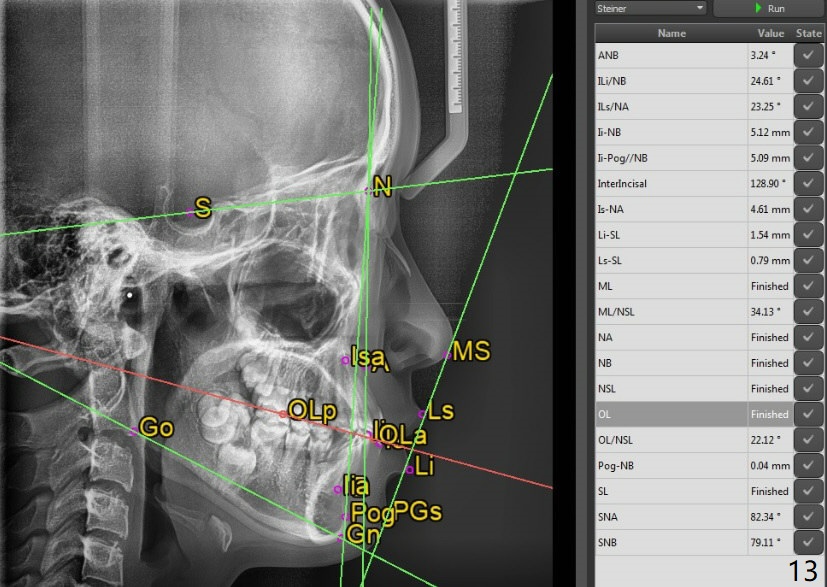

Facial Class I Occlusal Class II

A 12-year-old woman has Class I facial profile (Fig.1-4,12,13) and apparently Class II Division I malocclusion (Fig.6-11). Start Class II retraction as early as possible to take advantage of the upper and lower posterior diastemata (Fig.9,11 (in fact there is no diastema)). LL7 impaction is noted immediately prebanding (Fig.14). Surgical access is pending.